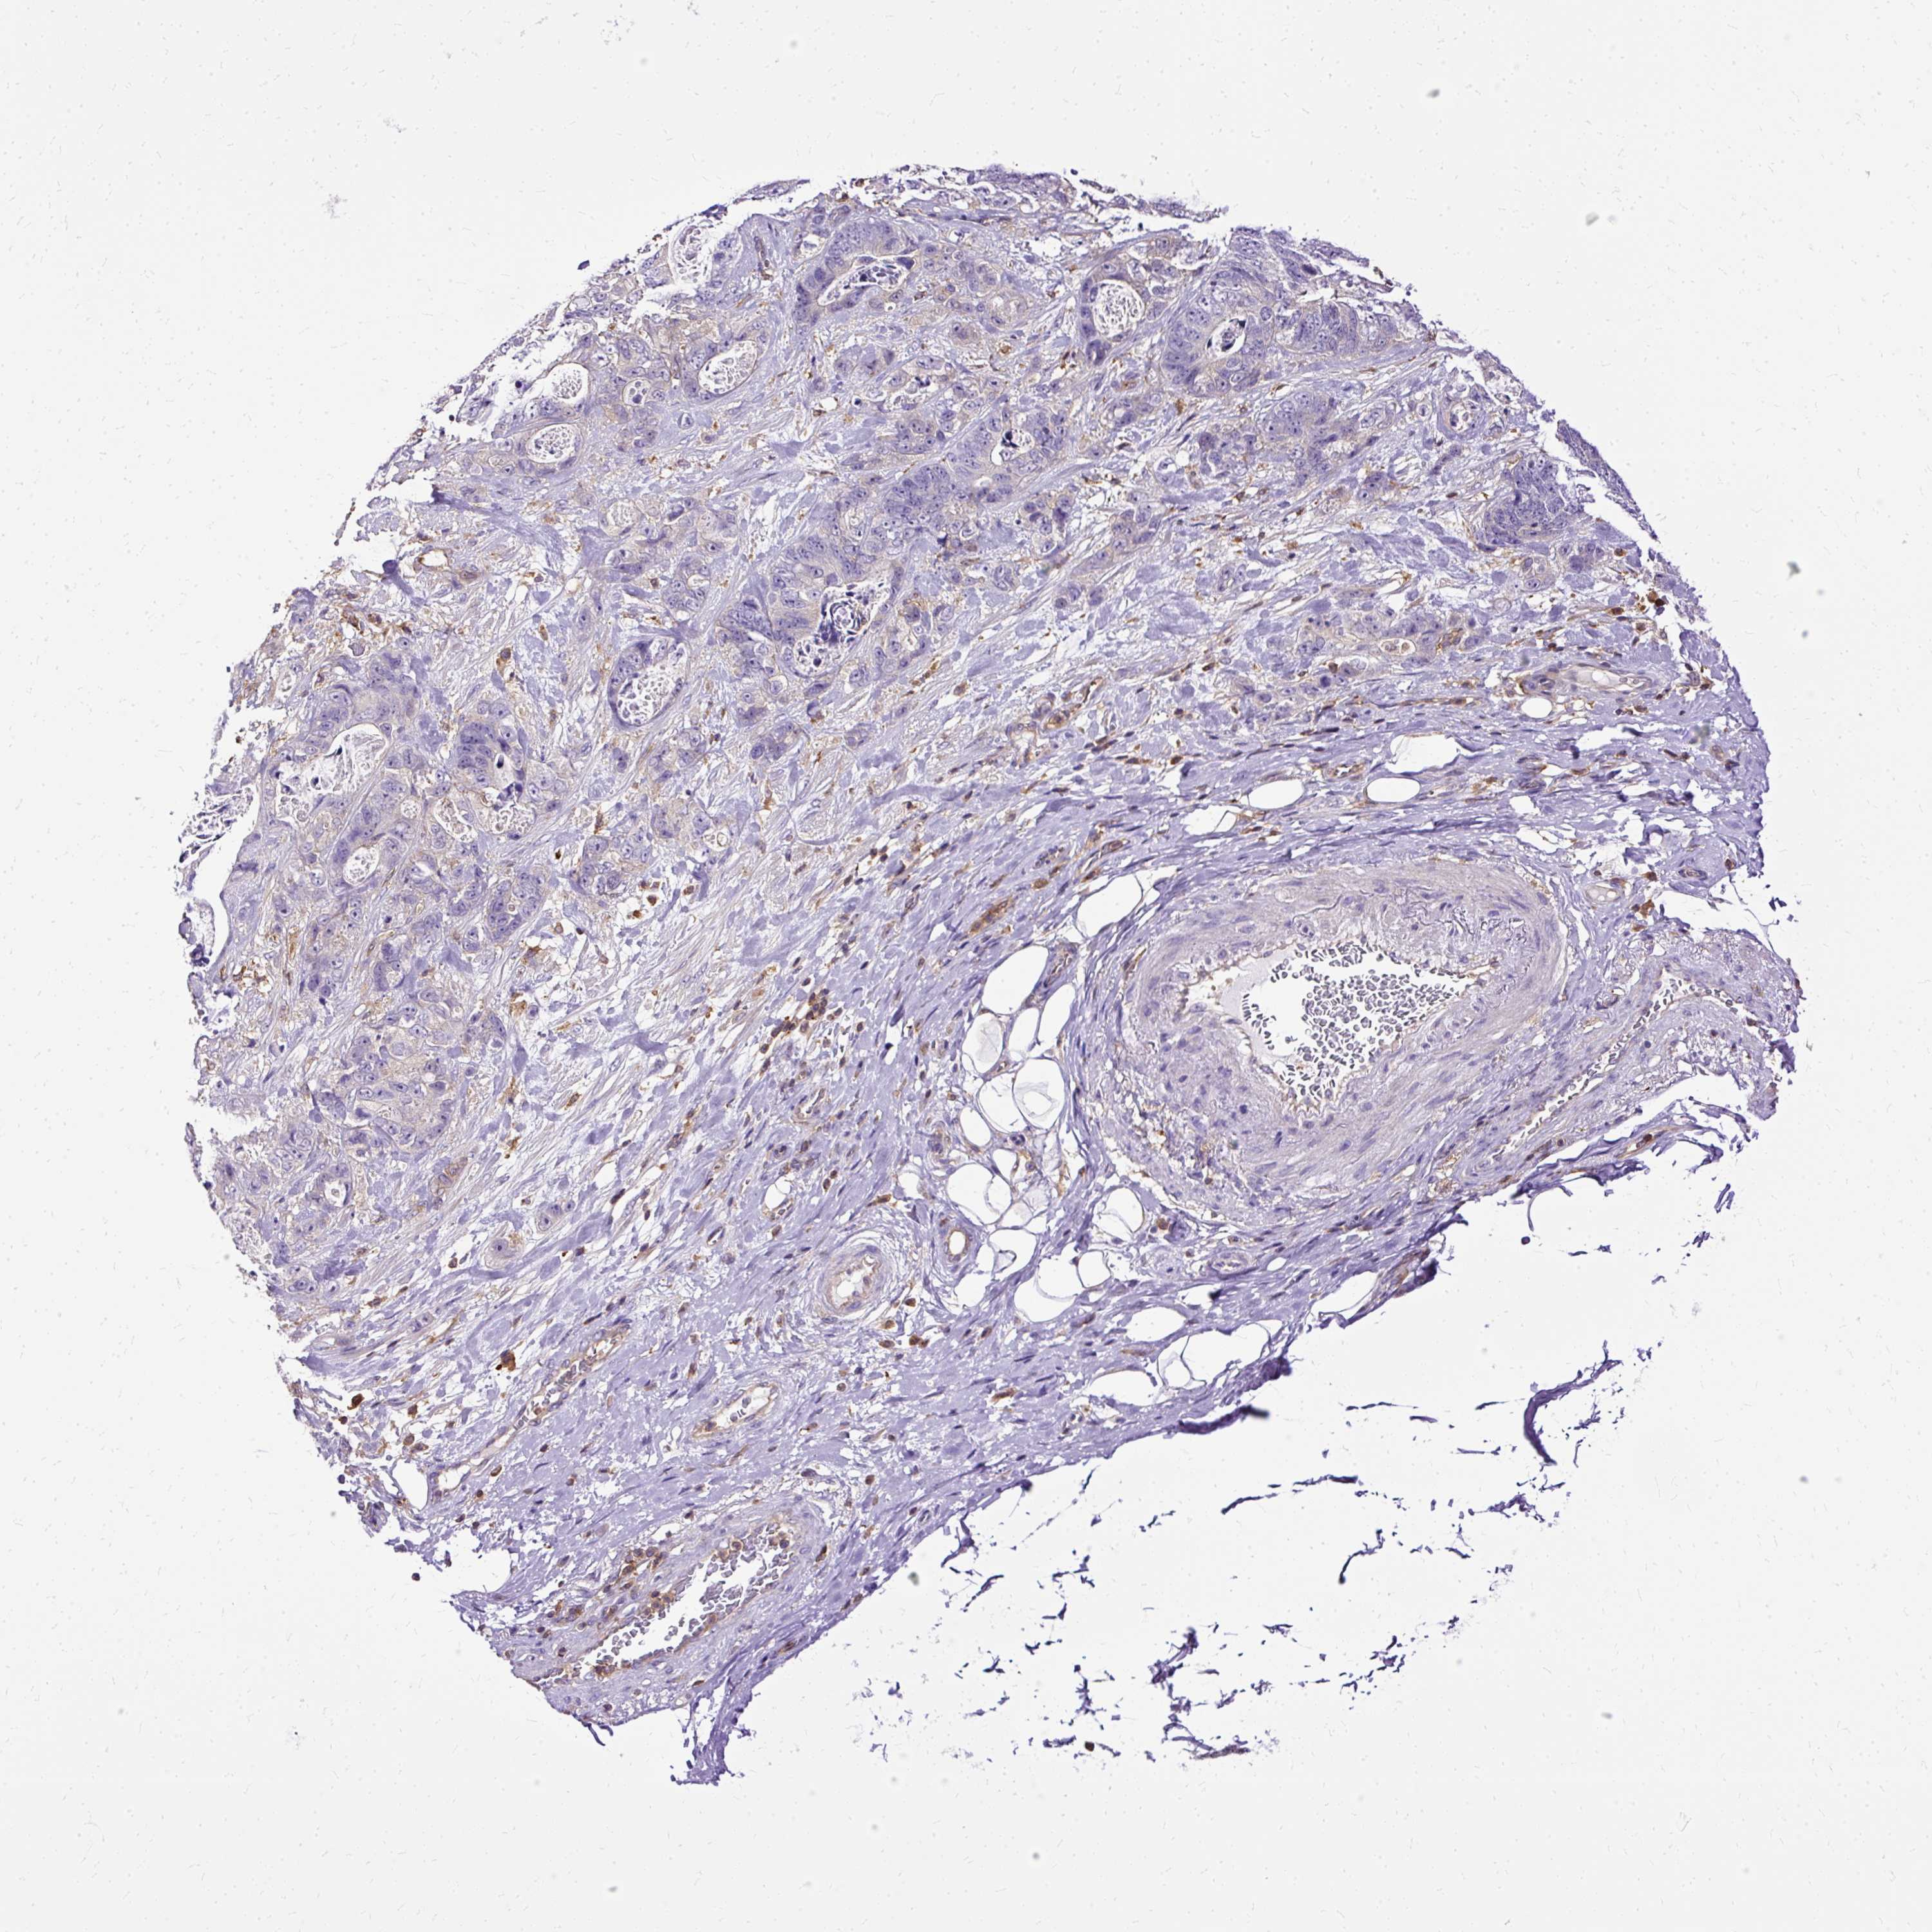

STOMACH CANCER - Protein expressioni

A mouse-over function shows sample information and annotation data. Click on an image to view it in a full screen mode. Samples can be filtered based on level of antibody staining by selecting one or several of the following categories: high, medium, low and not detected. The assay and annotation is described here.

Antibody stainingi

Antibody staining in the annotated cell types in the current human tissue is reported as not detected, low, medium, or high, based on conventional immunohistochemistry profiling in selected tissues. This score is based on the combination of the staining intensity and fraction of stained cells.

Each image is clickable and will lead to virtual microscopy that enables deeper exploration of all samples and also displays staining intensity scores, fraction scores and subcellular localization as well as patient and tissue information for each sample.

Antibody HPA053874

Staining

High

Medium

Low

Not detected

Intensity

Strong

Moderate

Weak

Negative

Quantity

>75%

75%-25%

<25%

None

Location

Nuclear

Cytoplasmic/membranous

Cytoplasmic/membranous,nuclear

Adenocarcinoma, NOS